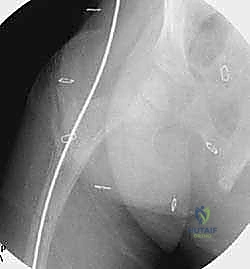

يتم إجراء العملية تحت التخدير العام. يتم وضع الطفل على طاولة العمليات الشفافة للأشعة، ويتم استخدام جهاز الأشعة السينية المستمر (C-arm) لضمان الدقة المطلقة خلال كل ثانية من العملية.

الخطوة الثالثة: بضع العظم المتعدد عبر الجلد (Multiple Percutaneous Osteotomies)

بدلاً من فتح الساق بالكامل، يقوم الدكتور هطيف بعمل ثقوب صغيرة جداً (مليمترات) في الجلد. باستخدام أدوات دقيقة جداً (مثل الإزميل الدقيق أو المثقاب المتخصص)، يتم قطع العظم في أماكن التقوس من الداخل دون إتلاف الأنسجة الرخوة أو العضلات المحيطة. هذا يحافظ على التروية الدموية للعظم (Periosteum)، مما يسرع من التئام العظم بشكل مذهل.

الخطوة الرابعة: إدخال المسمار التلسكوبي

بعد تقويم العظم وجعله مستقيماً كحبات المسبحة على خيط، يتم إدخال السلك الدليلي (Guide Wire). ثم يتم إدخال الجزء الخارجي (الأنثوي) من المسمار التلسكوبي وتثبيته في الجزء العلوي من العظم (Epiphysis).

بعد ذلك، يتم إدخال الجزء الداخلي (الذكري) من المسمار عبر الجزء السفلي من العظم وتثبيته في المشاشة السفلية. هذا التصميم العبقري يضمن حماية العظم بالكامل من الداخل.